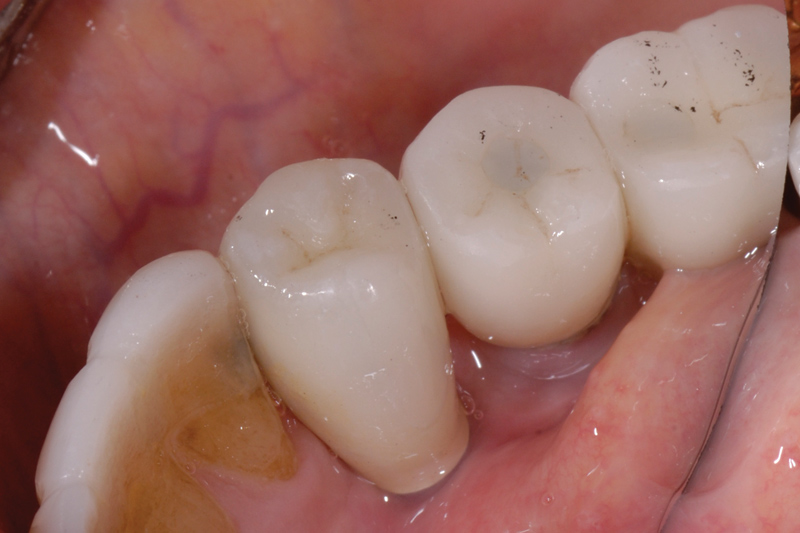

Cement application techniques in the luting of implant-supported crowns have also been scrutinized.26 Techniques appear to be used arbitrarily, with little understanding by clinicians regarding how or where to apply the cement. The practice of cementing restorations on natural teeth has been routinely performed for more than a hundred years with little issue, but very few clinicians have been trained or advised on the most appropriate place to load cement within a restoration. Because few, if any problems have been reported with the natural tooth, most clinicians have little concern for the amount of cement they use. However, implant restoration using cement is very different. A survey of more than 400 dentists reported little, if any, standardization of the amount of cement used.26 Some dentists placed over 30 times more cement than ideally required on the intaglio of the crown before it was seated (Figure 7). Others failed to achieve the minimum amount required (Figure 8).

Techniques have been developed to assist clinicians in approximating the right amount of cement.26 For example, pre-extrusion—extraorally with a custom copy abutment—is a quick, easy, and inexpensive method (Figure 9 through Figure 11).

Margin location is crucial in preventing residual excess cement extrusion into the peri-implant tissues. The work of Linkevicius et al has shown that even if the margin is placed 1 mm subgingivally, cement remnants will be left behind.14 Other solutions to the problem of cement extrusion include providing custom abutments with supragingival margins 360 degrees.27 The use of etchable ceramics that are esthetically compatible with the crown, silanation, and resin bonding reduces the chance of any cement material extrusion and allows for the use of such devices as rubber dam barrier protection,28 which further reduces the possibility of cement extrusion issues (Figure 12 and Figure 13). The author is currently studying abutment modifications, with a paradigm shift: instead of considering the margin of the abutment–crown as the only site where excess cement can be expressed, the screw-access channel is being contemplated as a repository capable of retaining cement within the system itself. Simple, inexpensive modification of abutment design that involves changing the way cement flows—by internalizing the flow with internal vents (Figure 14)—also reduces the amount of cement extrusion29 and alters the retentive properties of the cemented restoration.30 With zirconia, whose subtractive material changes may weaken the structure modifications to the screw channel itself, the use of an internal insert device is also being evaluated (Figure 15). The goal, again, is to internalize excess cement and alter flow, which can change the way the system works and which is something that cannot be done with the natural tooth. Finally, using a screw-retained crown eliminates the residual cement issue completely. Screw-retained restorations have been shown to be highly esthetic and to allow for complete control of the occlusion when fabricated correctly and judiciously (Figure 16 and Figure 17).31

Figure 11

Figure 12

Figure 13